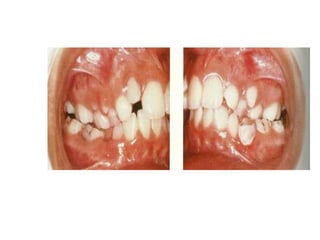

Consecuencias de la succión digital

• Protrusión de los incisivos superiores ( Con o sin

presencia de diastema).

• Retroinclinación de los incisivos inferiores.

• Mordida abierta anterior.

• Prognatismo Alveolar Superior.

• Estrechamiento del arcada superior ( Debido

principalmente a la acción del musculo

buccinador).

• Mordida cruzada posterior.

• Dimensión vertical aumentada.